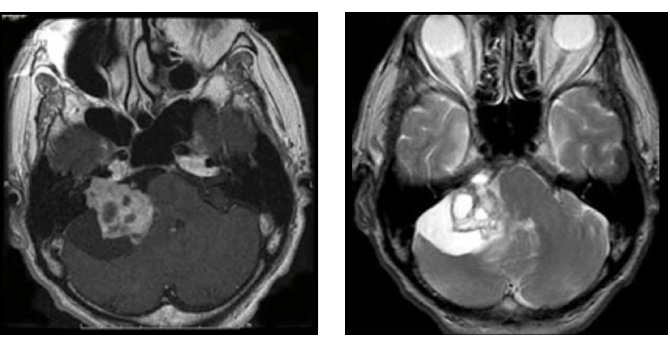

図3:50代男性 ガンマナイフ後3年半で拡大

(左図)ガンマナイフ時(中図)3年半後(右図)手術後 術後4年経過するも再増大なし

図3はガンマナイフ後、残念ながら増大してしまった50代男性の腫瘍です。聴覚はすでに失われておりましたので、注意深く顔面神経を保護しつつ手術を行い、95%摘出しました。術後問題なく社会復帰されています。